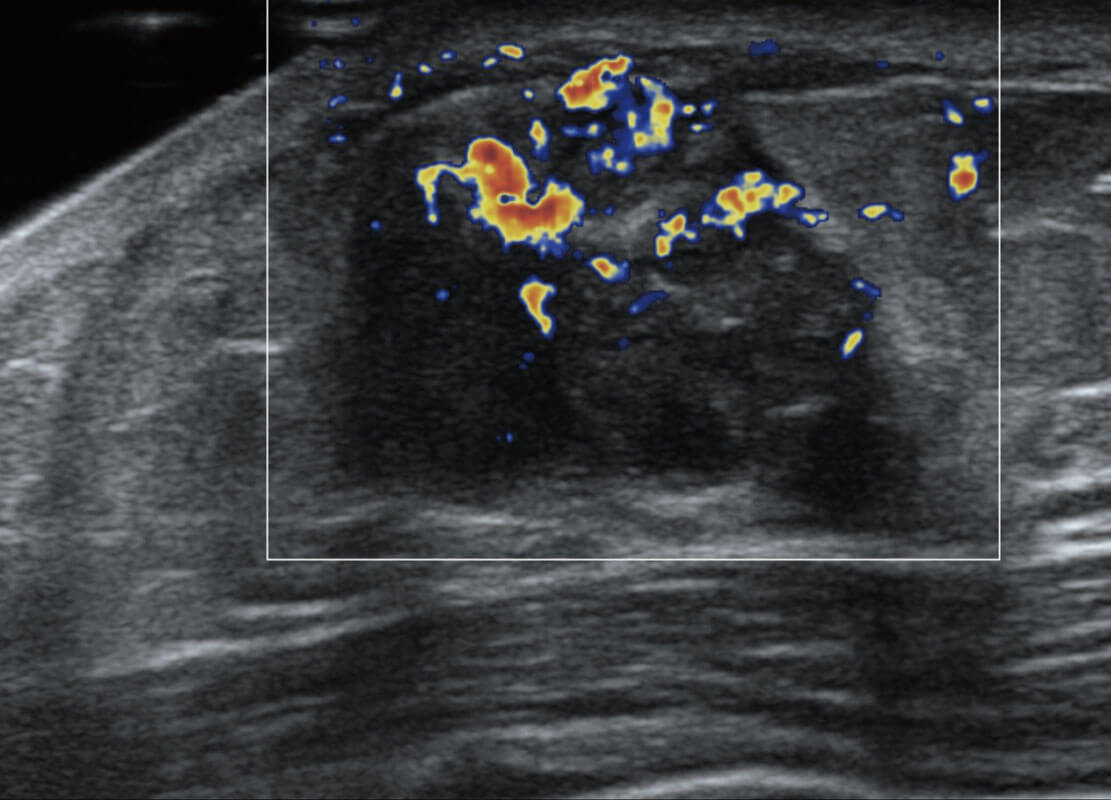

P60搭载宽频带线阵探头、宽景成像、弹性成像技术,为您提供乳腺应用方案。P60支持高频相控阵探头、线阵探头、腹部高频探头、腹部微凸探头等,丰富的探头群搭载敏感的彩色血流成像,适用于新生儿多种脏器检测要求,满足新生儿筛查需求。

乳腺导管癌

乳腺癌显微血流